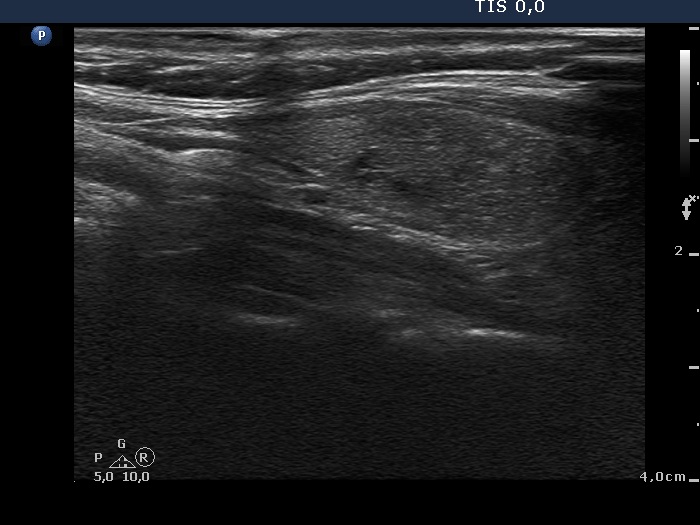

Benign Hashimoto's thyroiditis (cytological diagnosis) - case 1251

First, we demonstrate two cases of Hashimoto's thyroiditis with pronounced fibrotic changes. Both present pale and bright hyperechogenic granules and lines corresponding to normal and excessive connective tissue. Neither of the discrete areas are nodules in a pathological sense.